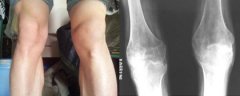

患者早年出现典型风湿性关节炎症状,膝关节疼痛、肿胀,未予重视。直到影响正常行走后,到...[详情]

陈先生是四川省攀枝花市的一名普通农民,五年前出现腰背、膝盖酸痛症状,起初以为是劳作过...[详情]